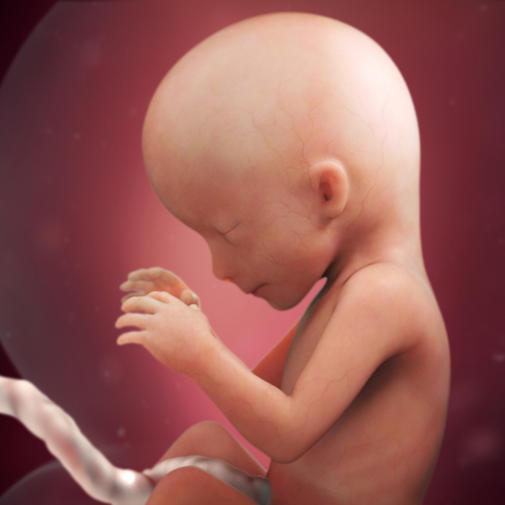

V 16. týdnu měří plod zhruba 11,5 cm. Při zjišťování délky plodu se měří vzdálenost od temene ke kostrči. Váha plodu je nyní zhruba 100 g.

Plod v 16. týdnu těhotenství (šipkami označena levá ruka s prstíky, paže, páteř).